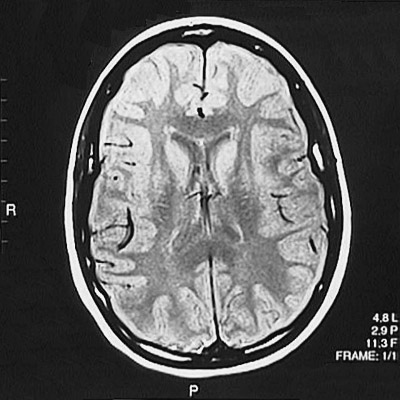

This is a normal axial proton density MRI scan demonstrating the frontal lobe and parietal lobe and genu of corpus callosum and splenium of corpus callosum and anterior horn of lateral ventricle and posterior horn of lateral ventricle and caudate and putamen and internal capsule and superior sagittal sinus.